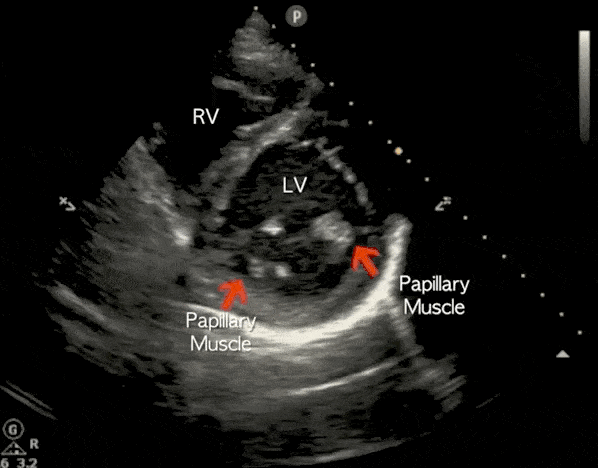

Echo Cardiography, also known as Echocardiography, is a non-invasive ultrasound test that uses sound waves to create real-time images of the heart. It helps doctors evaluate the structure, function, and blood flow of the heart accurately and safely.

Clinical Applications of Echo Cardiography

Cardiomyopathy